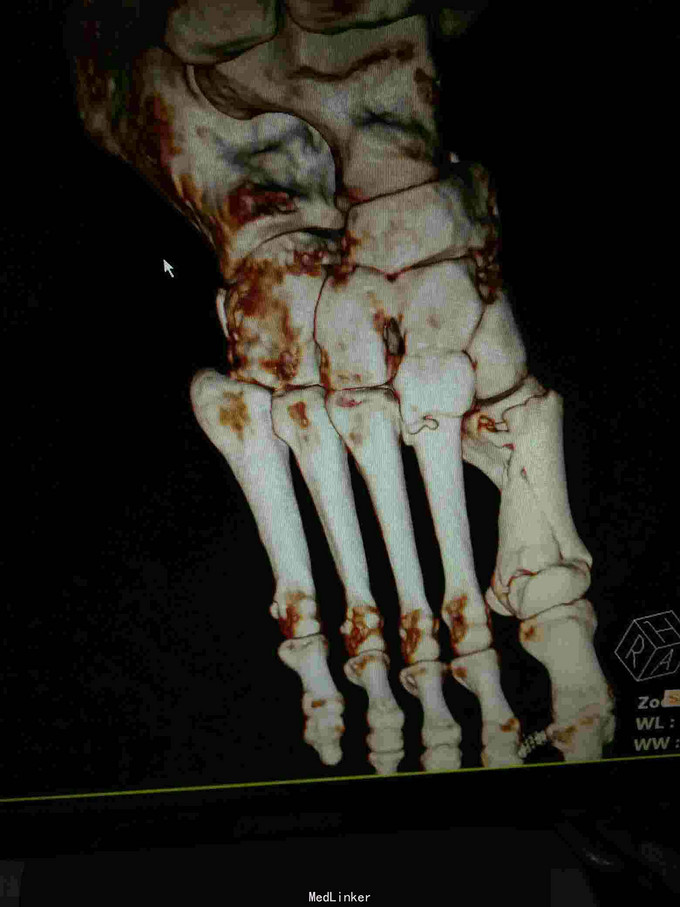

主诉:重物砸伤致右足疼痛伴活动受限2小时; 病史:患者不慎被重物砸伤右足,即感疼痛,活动受限,不能行走,不办皮肤破溃及活动性出血。

查体:右足畸形肿胀,足背少许擦挫伤,无开放性伤口,明显压痛,右足远远端感觉及血运可。 x片:右足第1、2跖骨基底部骨折,第3跖骨基底部可疑骨折; ct:右足第1~4跖骨骨折。

诊断:右足第1、2跖骨粉碎性骨折;右足lisfrance损伤; 治疗:石膏固定,消肿止痛,行右足跖骨骨折切开复位内固定,第1跖骨钢钉及克氏针固定,第2跖骨钢板固定。